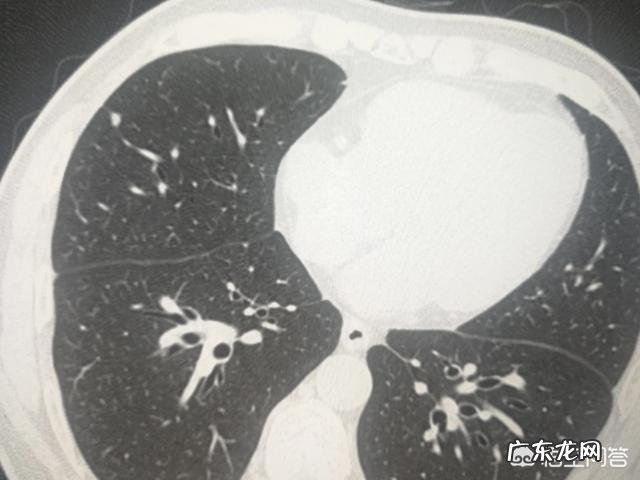

我是杨大夫,肺结节是指影像学上,现代主要是CT发现的 。圆形或类圆形的高密度影 。

如上图,就是典型的肺内淋巴结 。这种典型的结节,CT发现了,也不需要随访复查 。但需要放射科大夫的经验和胆识,以及医患双方的互信 。